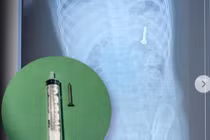

Từ khóa: Nguy cơ hóc dị vật trẻ nhỏ